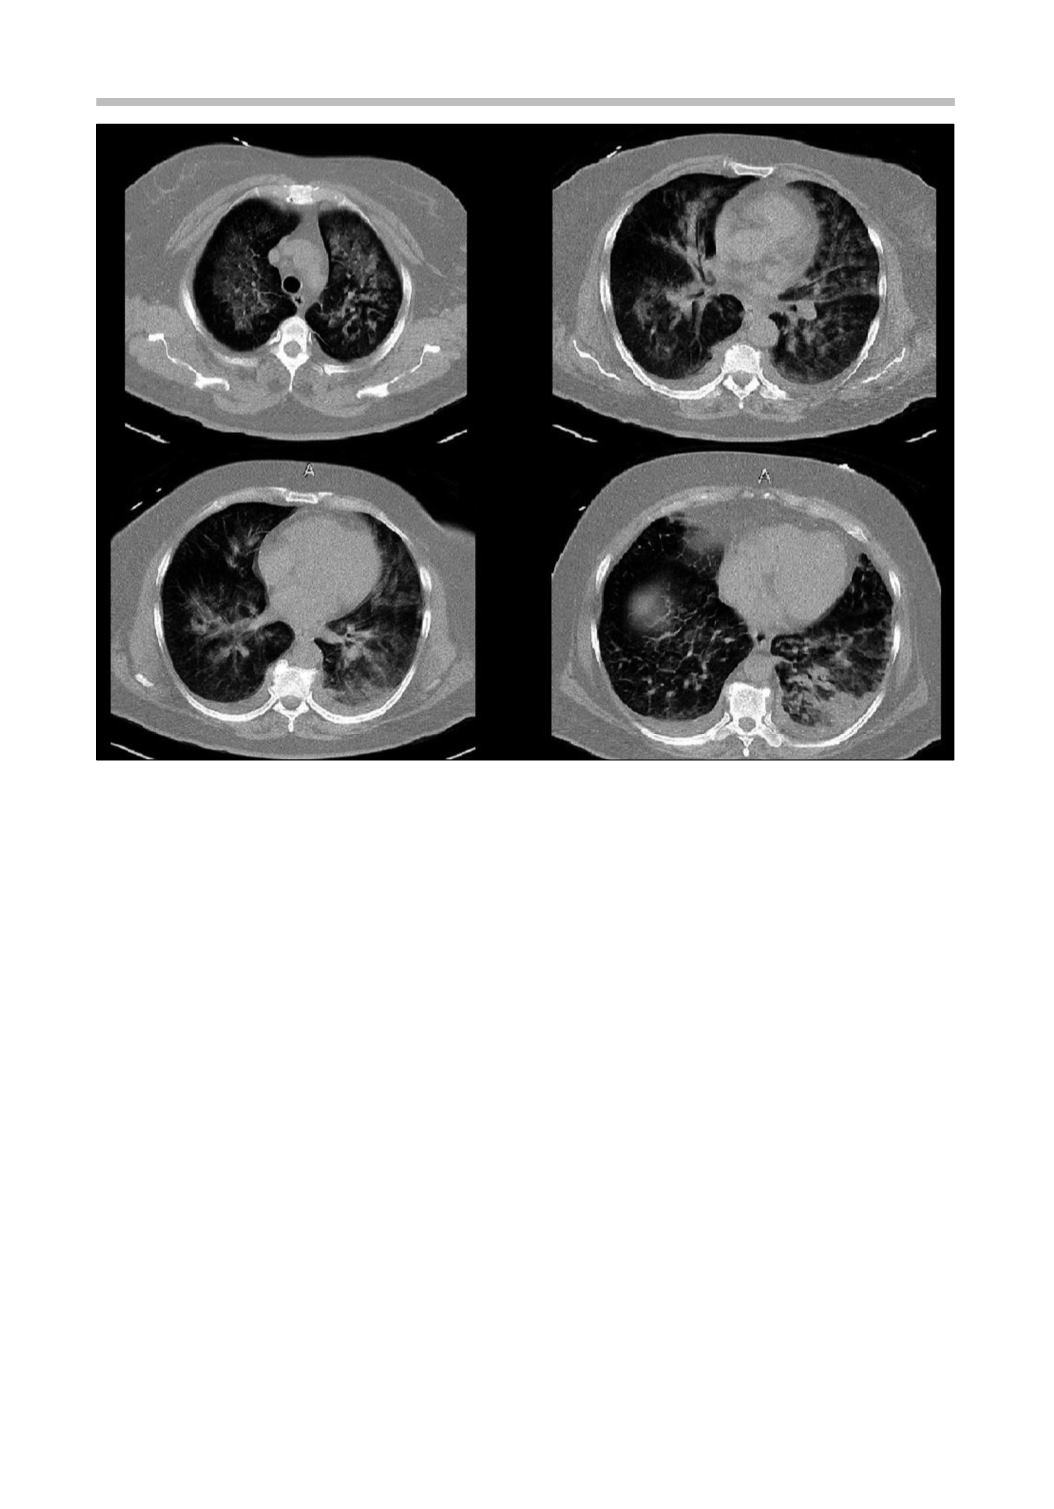

Figura 1.

Tomografía computada de tórax al ingreso (ver descripción en el texto).